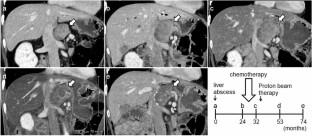

We report a case of a male in his 50 s who underwent pancreaticoduodenectomy for solid pseudopapillary neoplasm (SPN) of the pancreas at 30 years. He developed a liver abscess 15 years after the surgery, and CT scan revealed a swollen retroperitoneum lymph node and a tumor in the liver. Symptoms, including abdominal distension, appetite loss, and epigastric pain, appeared due to lymph node metastasis. Endoscopic ultrasonography-guided fine-needle aspiration against the lymph node revealed SPN recurrence. The tumor had invaded the common hepatic artery, and surgery was not indicated. Chemotherapy of Gemcitabine/nab-Paclitaxel biweekly was performed 8 times; however, no reduction in tumor size was observed, and the patient’s symptoms worsened. Proton beam therapy (67.5 GyE in 25 fractions) was subsequently performed for lymph node metastasis, and led to a gradual reduction in lymph node metastasis, and an improvement in symptoms. No re-expansion of lymph node metastasis has been observed 3 years after proton beam therapy. Since SPN is low malignancy and most cases can be expected to be cured by surgery, there is currently no standard treatment of unresectable SPN. This case is the first report of proton beam therapy for SPN, and was considered to be effective.

Fig. 1